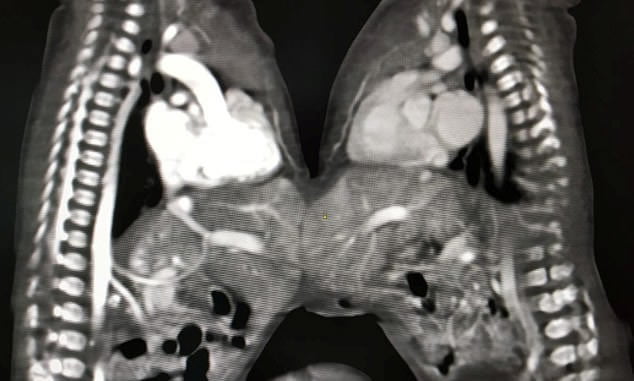

2018年12月15日連體嬰兒非常罕見,但世界各地都曾出現過。印度就有一對連體雙胞胎女嬰,她們的胃部相連,出生3天體重只有3公斤。醫生認為通過手術將兩個嬰兒分離是最好的選擇。父母擔心手術有危險,但最後還是被醫生說服了。

▼5名外科醫生、10名醫生和15名護士共同努力了5個小時,手術終於成功了。這兩個女嬰很快就可以出院。因為孩子的父母無力承擔醫療費用,醫院決定免費為她們做手術。

▼醫院的Vaibhav Pandey博士說:「這是我們醫院做過的最罕見的手術之一,很有挑戰性。最後這兩個女嬰成功獲救,我們都很高興。」